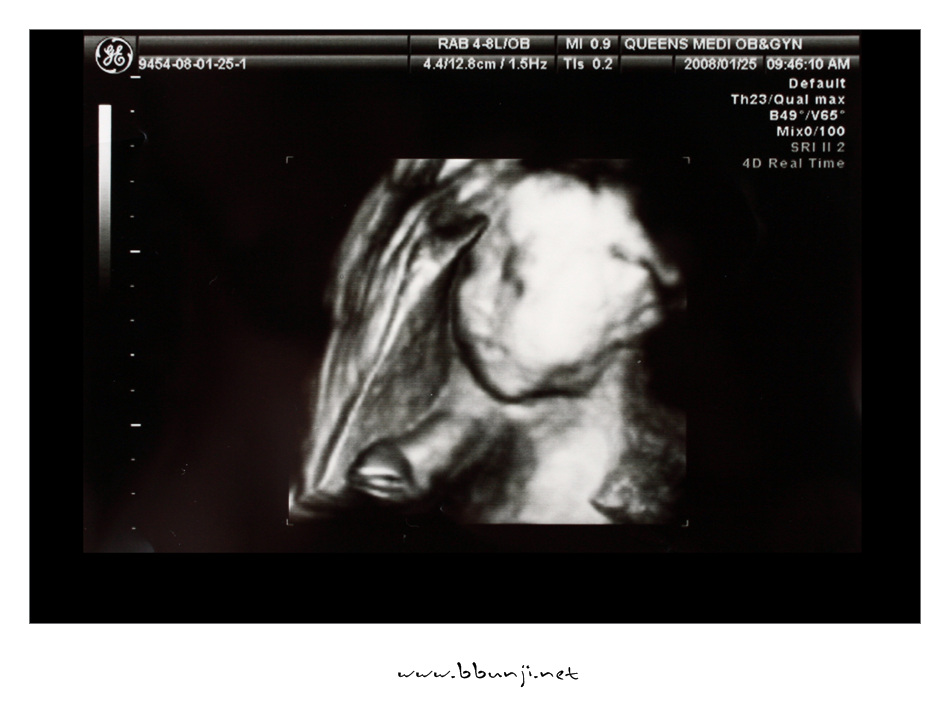

사랑이… 24주 째.. *^^*

2008년 01월 25일

이번에 입체 초음파 한다고 어찌나 기대를 하고 갔는지~~

얼굴 가리고 다리 움직이고 초음파 하면서도 막 움직이는게 너무 희안합니다.

코도 오똑한거 같고 입술도 이쁘게 생겼고…

얼굴 갸름한거랑 발 모양은 엄마 닮은거 같고 손가락도 긴거 같고 ㅋㅋㅋ

이번에는 갔더니 길이는 초음파에 한번에 안 잡혀서 알 수 없고 몸무게는 760g 정도 나간다고 하더라구요.

주수에 맞게 아주 잘 크고 있다고 초음파 사진보니 그나마 얼굴에 살이 조금 붙은듯…